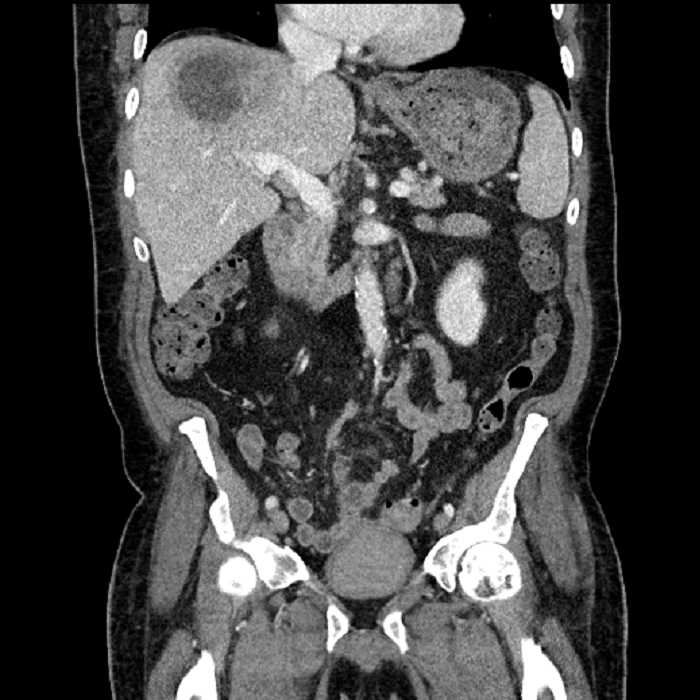

• Large fluid density structure in hepatic segments 7 and 8 measuring 10 x 7 x 7 cm with internal septation and circumferential ill-defined low density compatible with edema

• Peripherally enhancing subcapsular collections along the anterior margin of the left hepatic lobe measuring 3 x 1 cm and 2 x 1 cm

Acute sigmoid diverticulitis complicated by a small contained perforation and a large abscess in the right hepatic lobe. Additional small subcapsular abscesses along the anterior margin of the left hepatic lobe.

• The classic CT imaging appearance is a double target sign with internal low density surrounded by an internal enhancing rim (capsule) and a low density external rim (edema)

Hepatic abscess showing the double target sign with low density internally surrounded by a thin inner enhancing rim (red arrow) and ill-defined outer low density rim (yellow arrow). Blue arrow indicates an internal septation. Red arrows: additional smaller subcapsular abscesses. Red arrow: focal contained perforation associated with diverticulitis.